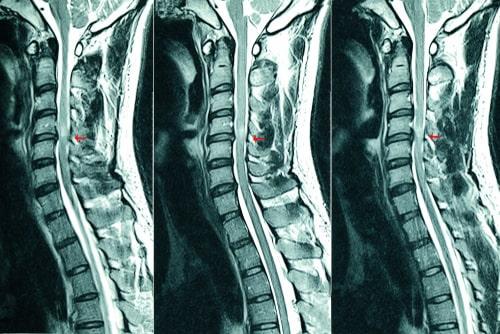

1. Whiplash and Neck Injuries

In a truck accident, the sudden impact can cause the head to jerk forward, backward, or to the side forcefully. This places a great deal of strain on the neck muscles and ligaments, and it may also cause damage to the nerves in the neck and shoulders. Neck injuries can cause multiple types of ongoing symptoms, including pain, stiffness, headaches, dizziness, and reduced range of motion. Nerve damage may also result in numbness, tingling, or paralysis in the shoulders, arms, and hands.